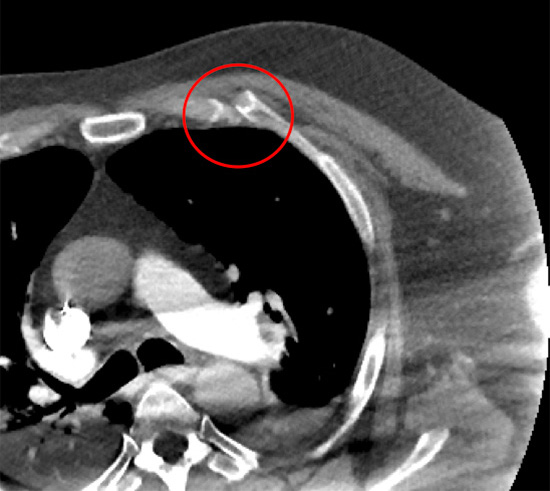

Manubriosternal junction or Sternal angle (highlighted with red circle)

The maubriosternal junction can be injured through a direct blow or indirectly through acceleration-deceleration compressive-decompressive type of injury (for example during a front on collision in a seat belted passenger). This results in a dislocation and can lead to severe pain, tenderness and swelling (a step) in the area. If such an injury is suspected a chest CT scan is required to diagnosis and to assess for other chest injuries.

A more insidious problem is the development of localised inflammation in the area leading increasing pain, discomfort and occasionally the area can be hot or swollen. A high clinical suspicion is regarded and together with radiological investigations such as an MRI.